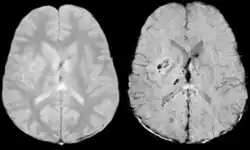

Comparison of diffuse axonal injury imaged with conventional GRE (left) and SWI (right) at 1.5 T

Comparison of hemorrhage imaged with conventional GRE (left) and SWI (right) at 1.5 T

The detection of micro-hemorrhages, shearing, and diffuse axonal injury (DAI) in trauma patients is often difficult as the injuries tend to be relatively small in size and can be easily missed by low resolution scans. SWI is usually run at relatively high resolution (1 mm3) and is extremely sensitive to bleeding in the gray matter/white matter boundaries making it is possible to see very small lesions increasing the ability to detect more subtle injuries.

Stroke and hemorrhage

Diffusion weighted imaging offers a powerful means to detect acute stroke. Although it is well known that gradient echo imaging can detect hemorrhage, it is best detected with SWI. In the example shown here, the gradient echo image shows the region of likely cytotoxic edema whereas the SW image shows the likely localization of the stroke and the vascular territory affected (data acquired at 1.5 T).

The bright region in the gradient echo weighted image shows the area affected in this acute stroke example. The arrows in the SWI image may show the tissue at risk that has been affected by the stroke (A, B, C) and the location of the stroke itself (D). The reason that we are able to see the affected vascular territory could be because there is a reduced level of oxygen saturation in this tissue, suggesting that the flow to this region of the brain could be reduced post stroke. Another possible explanation is that there is an increase in local venous blood volume. In either case, this image suggests that the tissue associated with this vascular territory could be tissue at risk. Future stroke research will involve comparisons of perfusion weighted imaging and SWI to learn more about local flow and oxygen saturation.